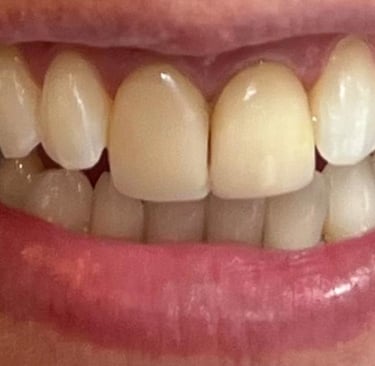

Cirurgia de aumento de coroa clínica antes das coroas

Caso que demonstra a vantagem da integração de diversas áreas da odontologia, unindo cirurgia, periodontia, prótese e estética para alcançar resultados funcionais e harmônicos.

Antes

Depois